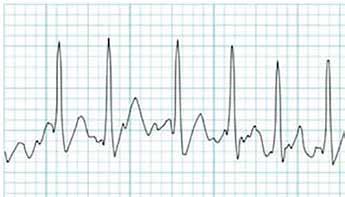

52 EKG 101